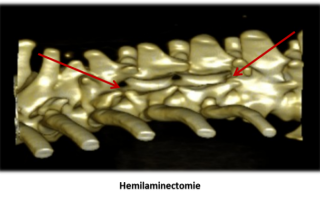

Chirurgie de la colonne vertébrale

- Hernies discales

- Syndrome de Wobbler (instabilité cervicale caudale)

- Instabilité vertébrale

- Chirurgie cancéreuse

Consultations de neurologie avec scanner/IRM puis chirurgie de la colonne : hernies discales, instabilité cervicale caudale (Wobbler), instabilité lombo-sacrée, tumeurs vertébrales.

Parcours intégré imagerie-bloc pour limiter délais et risques